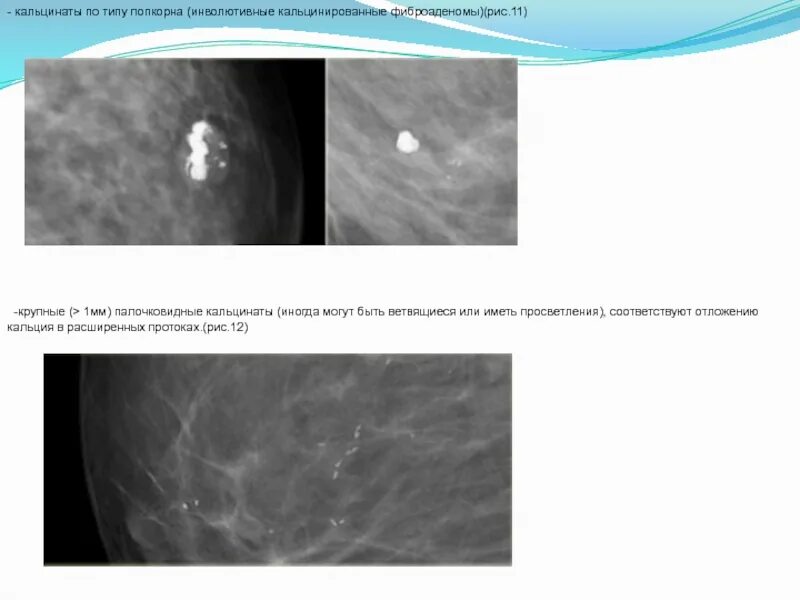

Микрокальцинаты в молочной железе что это